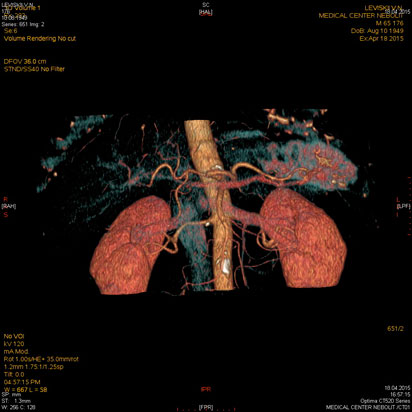

МСКТ почек, надпочечников

- Дифференциальная диагностика объемных образований почек

- Стадирование опухолей

- Стенозы почечных артерий

МСКТ надпочечников, почек

Показания:

- подозрение на опухоль почек, надпочечников, забрюшинного пространства